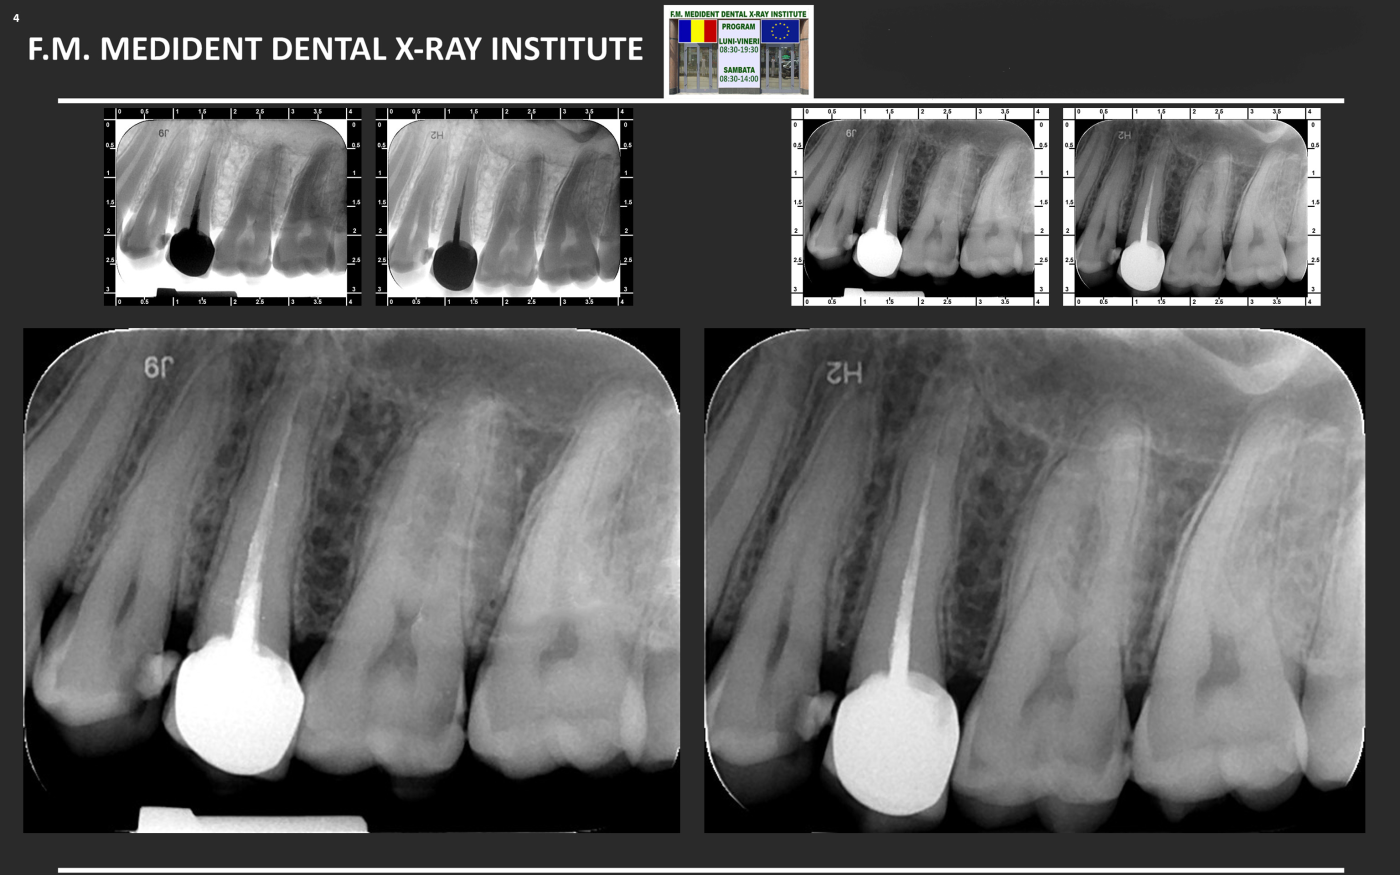

Aspectul radiologic dupa tratamentul de canal, inserarea pivotului si cimentarea coroanei definitive.

Cazul 2.